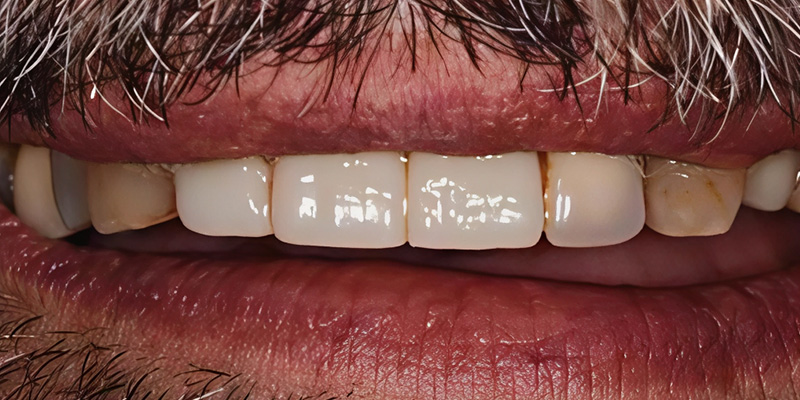

Fig. 10 : Provisoire le jour de la chirurgie.